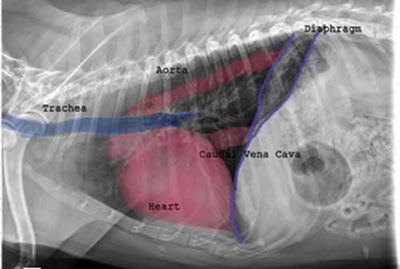

Radiography (x-ray) is used to determine if the heart is enlarged

(particularly the left atrium and left ventricle), if the veins from the

lungs to the heart are distended, or if fluid is beginning to develop in the

lungs.* X-rays also will show any enlargement of

the pulmonary vein, a classic symptom of congestive heart failure (CHF).

• Using radiography to diagnose heart enlargement

Mild to moderate heart enlargement indicates mild to moderate progression of mitral regurgitation (MR), with the heart compensating for the effects of mitral regurgitation by enlarging. Usually the dog displays no outward signs or symptoms of MVD when moderate to severe heart enlargement develops, until the dog reaches the stage of heart failure.